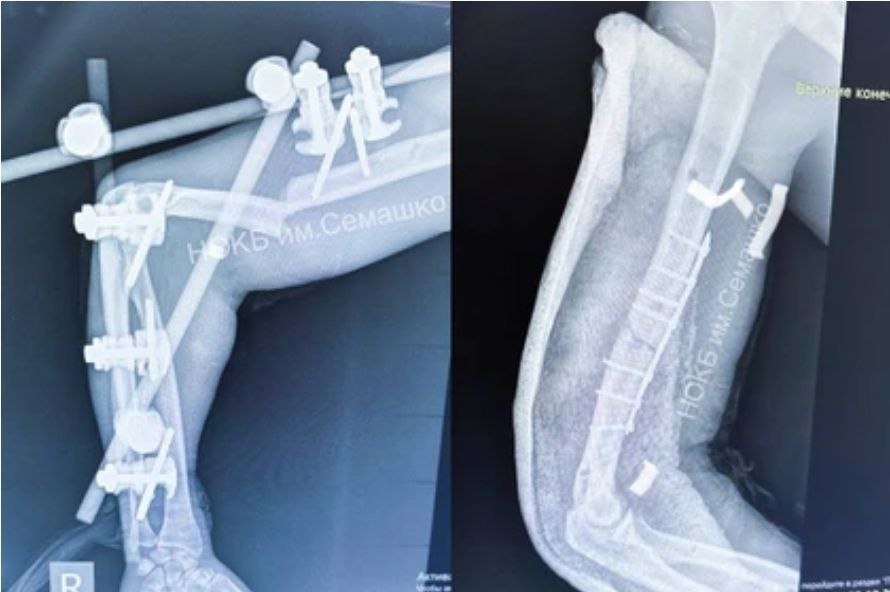

Упал с 32-го этажа и остался жив. В ноябре прошлого года на одной из строительных площадок Нижнего Новгорода произошло страшное происшествие – монтажник сорвался с 32-этажа строящегося небоскреба. Хирурги два месяца заново собирали скелет рабочего. Монтажника спасло защитное сооружение, на него он рухнул пролетев 20 этажей. Получил 10 переломов: носа, обоих плечей, ребер, костей таза и ног. Одно легкое оказалось разорванным. К жизни пациента вернули в НОКБ им. Семашко.  📘 Блог 🔤🔤🔤/ Подписаться 🇷🇺